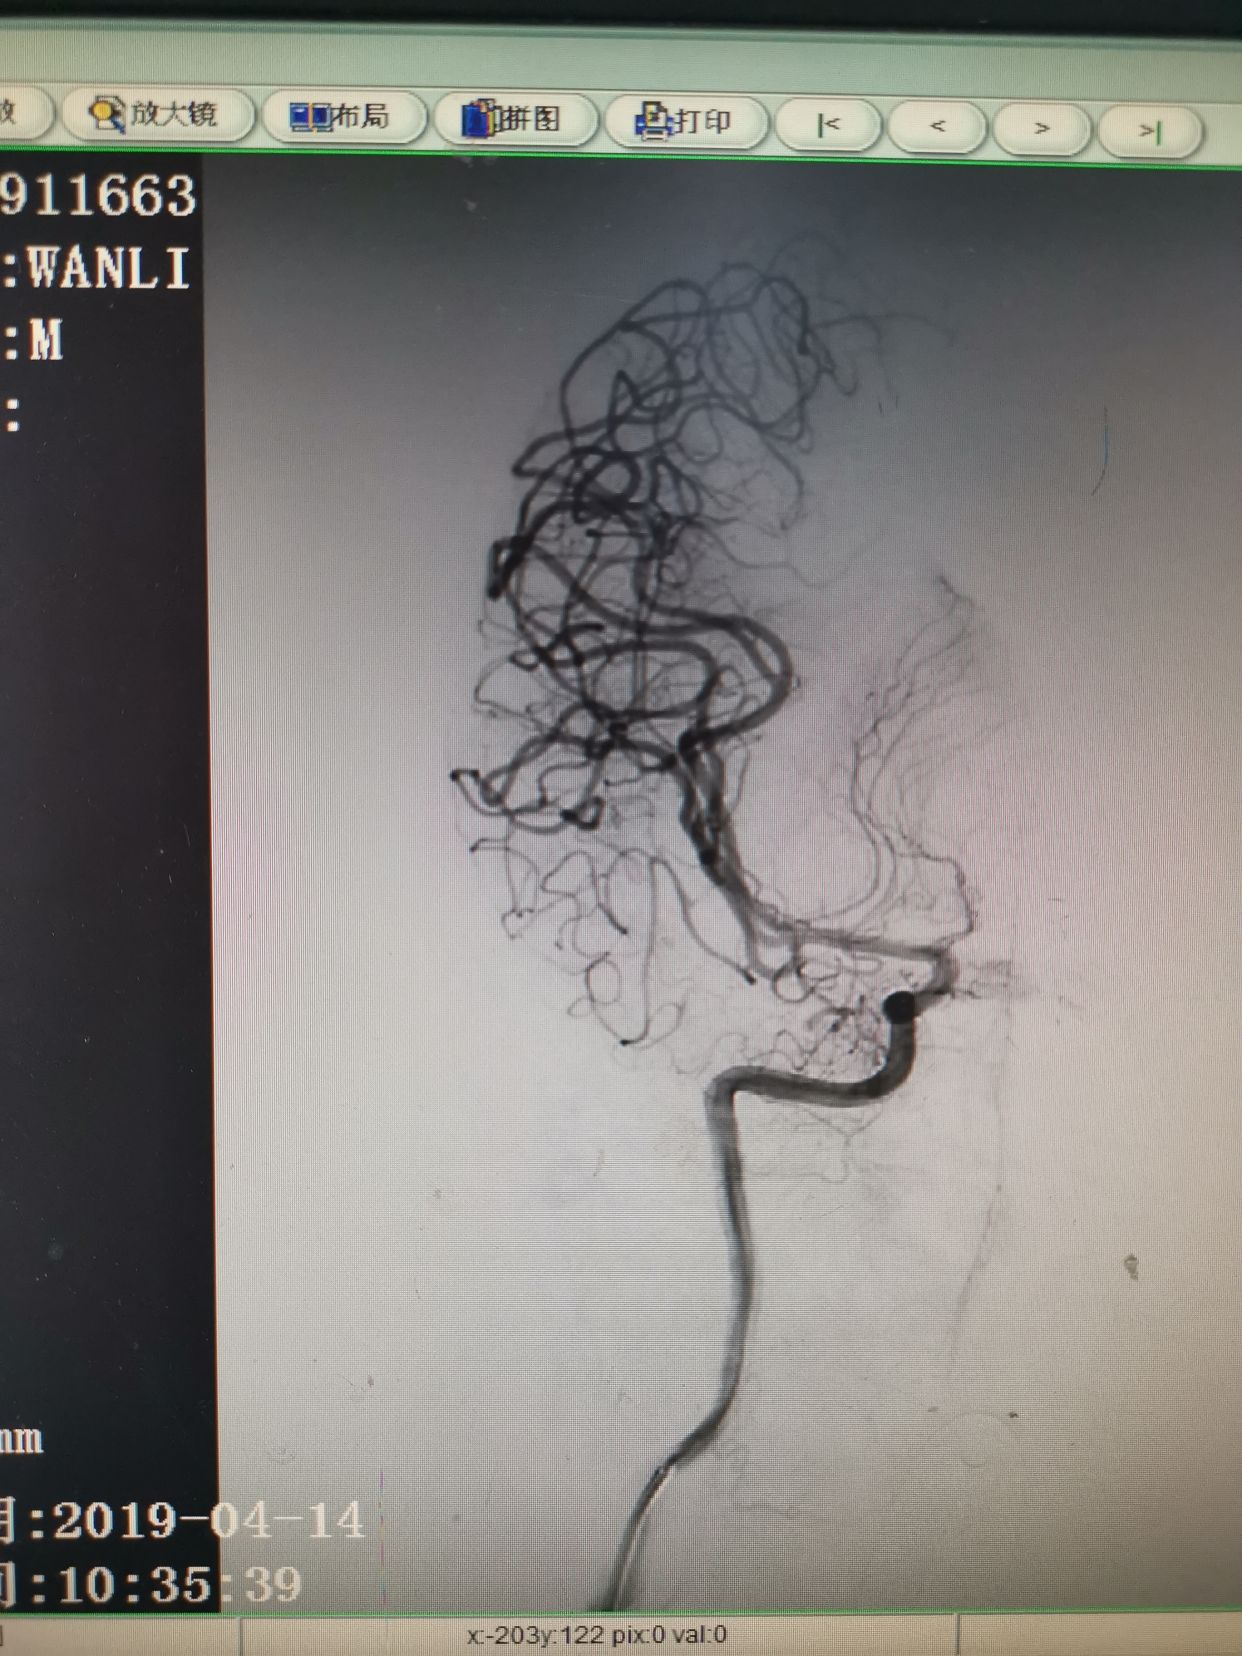

右侧颈内动脉造影。